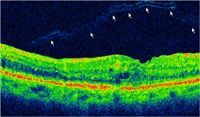

Mujer de 82 años con retinopatía diabética no proliferativa leve-moderada y sin edema macular clínicamente significativo (EMCS) en AO, con antecedentes de ambliopía en OD. Explicaba un control glicémico irregular. La paciente fue intervenida de catarata bajo anestesia tópica en AO con un intervalo de 6 meses entre cada ojo, sin incidencias operatorias. La AV tras la intervención de catarata fue de 0.5dif en OD y 0.25 dif en OI con corrección óptica. La paciente presentaba una retinopatía diabética no proliferativa (RDNP) leve-moderada desarrollando en el postoperatorio un leve edema macular (EM) en AO acompañado de metamorfopsia en OI, que requirió la realización de angiografía fluoresceínica (AGF) y tomografía de coherencia óptica (OCT) macular (

Figura 1 y

Figura 2 ).

Figura 2. OCT macular OI donde se aprecia con nitidez la tracción que la hialoides posterior ejerce sobre la retina interna